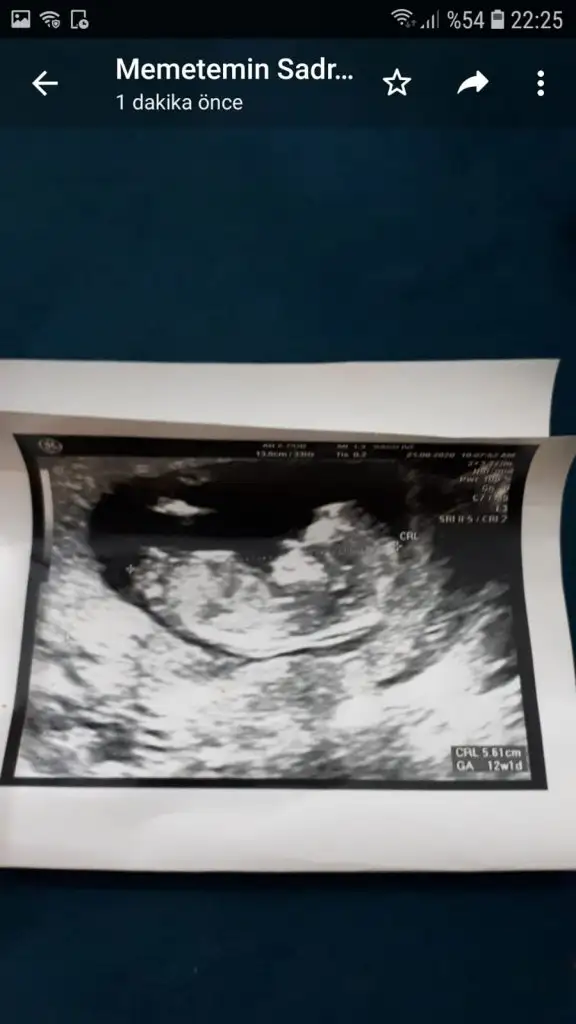

20200916_174747.jpg bunu atmıştım en son 😁😁

Eki Görüntüle 2695934 bunu atmıştım en son 😁😁

20200921_114838.webp bunda bacaklarini gostermiyordu ama sadece govde ve kafa . Kafasini asagiya sıkıştırms yaramaz 😄

Eki Görüntüle 2695937 bunda bacaklarini gostermiyordu ama sadece govde ve kafa . Kafasini asagiya sıkıştırms yaramaz 😄